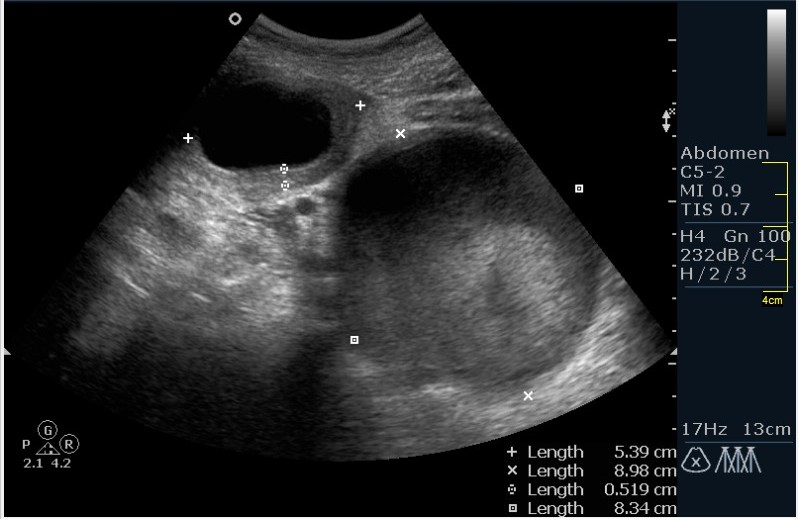

Девочка 12 лет; жалобы на частое мочеиспускание; тупые, тянущие боли в малом тазу. Менструацию отрицает. УЗИ малого таза, все сонограммы выполнены по средней линии, в поперечной и сагитальной проекциях.

Гематокольпос при заращении девственной плевы. Менархе. Врожденная аномалия половых органов.